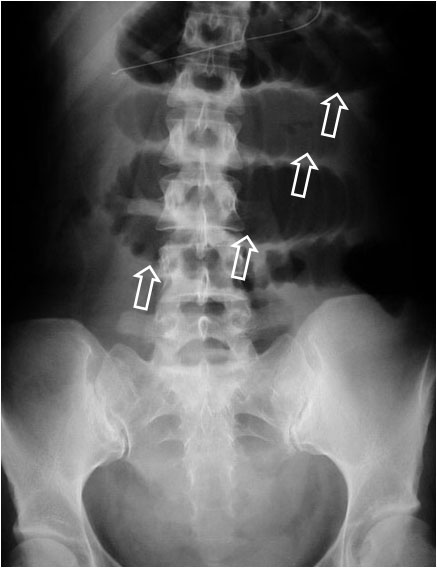

SIGNO DE LA ESCALERA

Signo visto en la radiografía simple de abdomen en la obstrucción intestinal, llamado así por el aspecto de las asas intestinales dilatadas y rellenas de aire, superpuestas unas sobre otras (flechas).